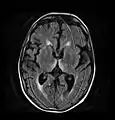

Brain atrophy associated with WKS occurs in the following regions of the brain:

1. the mammillary bodies,

2. the thalamus,

3. the periaqueductal grey,

4. the walls of the 3rd ventricle,

5. the floor of the 4th ventricle,

6. the cerebellum, and

7. the frontal lobe.

In addition to the damage seen in these areas there have been reports of damage to cortex, although it was noted that this may be due to the direct toxic effects of alcohol as opposed to thiamine deficiency that has been attributed as the underlying cause of Wernicke-Korsakoff Syndrome.[25]

The amnesia that is associated with this syndrome is a result of the atrophy in the structures of the diencephalon (the thalamus, hypothalamus and mammillary bodies), and is similar to amnesia that is presented as a result of other cases of damage to the medial temporal lobe.[26] It has been argued that the memory impairments can occur as a result of damage along any part of the mammillo-thalamic tract, which explains how WKS can develop in patients with damage exclusively to either the thalamus or the mammillary bodies.[25]

Frequently, secondary to thiamine deficiency and subsequent cytotoxic edema in Wernicke encephalopathy, patients will have marked degeneration of the mammillary bodies. Thiamine (vitamin B1) is an essential coenzyme in carbohydrate metabolism and is also a regulator of osmotic gradient. Its deficiency may cause swelling of the intracellular space and local disruption of the blood-brain barrier. Brain tissue is very sensitive to changes in electrolytes and pressure and edema can be cytotoxic. In Wernicke this occurs specifically in the mammillary bodies, medial thalami, tectal plate, and periaqueductal areas. People with the condition may also exhibit a dislike for sunlight and so may wish to stay indoors with the lights off. The mechanism of this degeneration is unknown, but it supports the current neurological theory that the mammillary bodies play a role in various "memory circuits" within the brain. An example of a memory circuit is the Papez circuit.